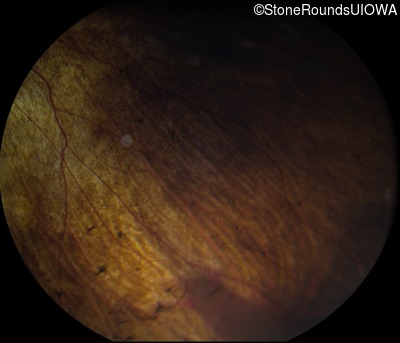

Fundus Photography - Left - 20/30

Exemplar

Fundus Montage - Left - 20/30